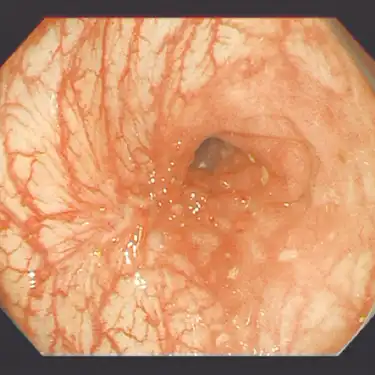

狭窄部に対する内視鏡拡張術 -

病気の予後はいかに早期に発見し腸の状態をよくできるかで決まるとされますが、進行した状態でも治療薬や外科手術、内視鏡手術の進歩により生活の質を向上できる患者さんが増えています。とりわけ2002年から使用可能となった生物学的製剤(注射薬)により大幅に予後が改善しており、最近では副作用と効果のバランスに優れた治療薬も使用可能となっています。